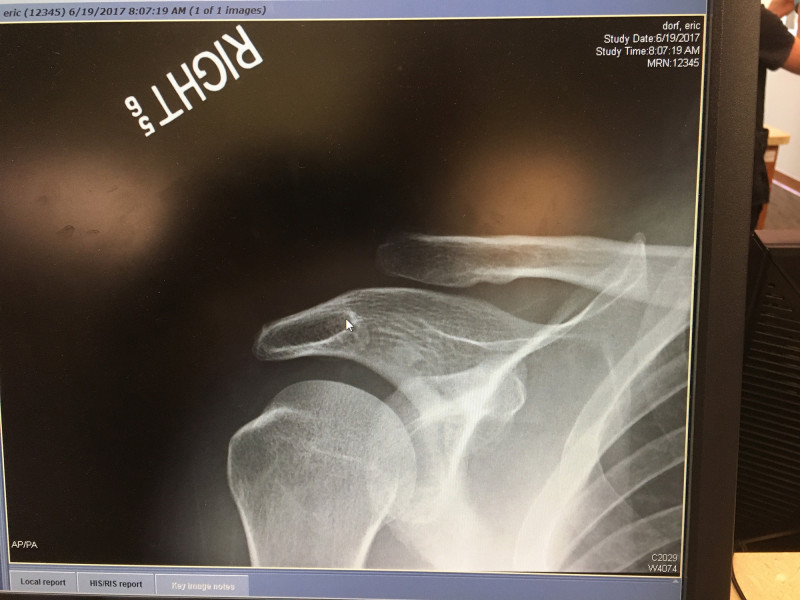

You should never try to sprint against a fast sprinter on your bike. Trying to race my son Mack, I came out of my pedal and went over the bars.

The result: Grade 3 AC separation.

No surgery on this one thank god. Lesson learned.